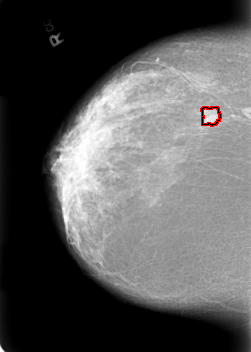

B_3020_1.RIGHT_CC

RIGHT_CC LINES 5624 PIXELS_PER_LINE 4008 BITS_PER_PIXEL 12 RESOLUTION 50 OVERLAY

FILE: B_3020_1.RIGHT_CC.OVERLAY

TOTAL_ABNORMALITIES 1

ABNORMALITY 1

LESION_TYPE MASS SHAPE LOBULATED MARGINS CIRCUMSCRIBED-ILL_DEFINED

ASSESSMENT 4

SUBTLETY 4

PATHOLOGY MALIGNANT

TOTAL_OUTLINES 1

BOUNDARY